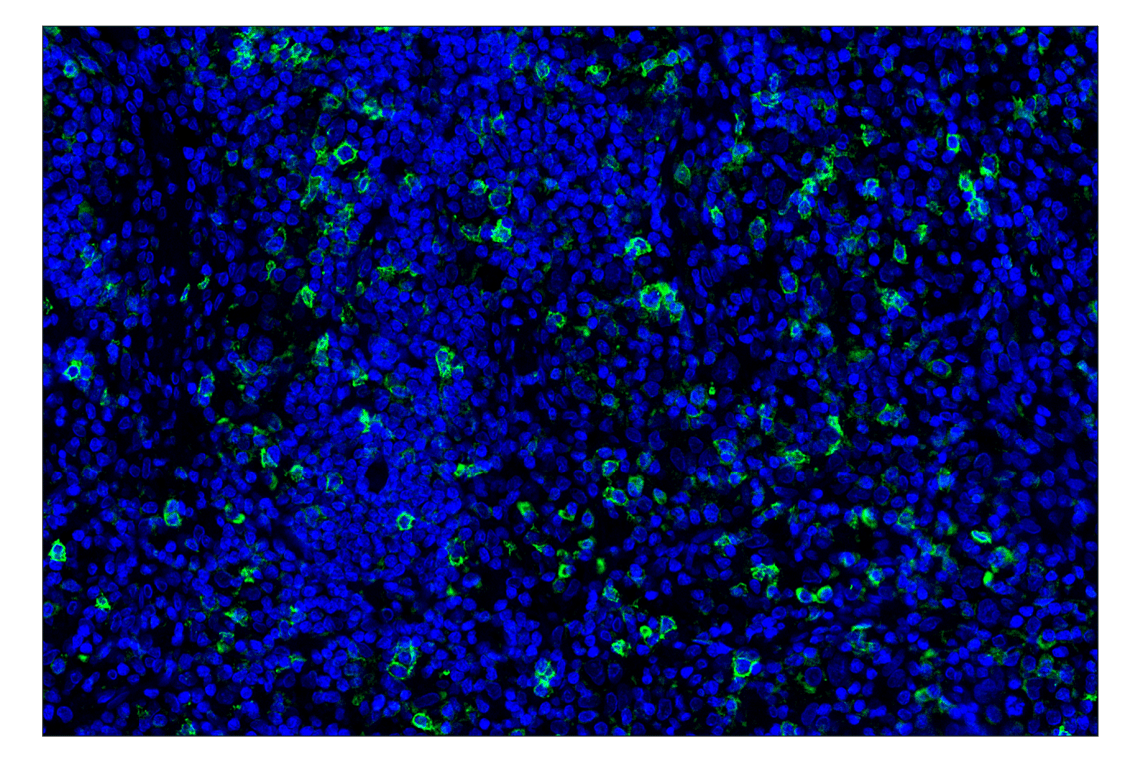

ICOS (D1K2T) Rabbit Monoclonal Antibody (Alexa Fluor® 488 Conjugate) #35988

Immunohistochemistry (Paraffin) 1:50 - 1:200

ICOS (D1K2T) Rabbit Monoclonal Antibody (Alexa Fluor® 488 Conjugate) detects endogenous levels of total ICOS protein.

Species Reactivity:

Human, Monkey